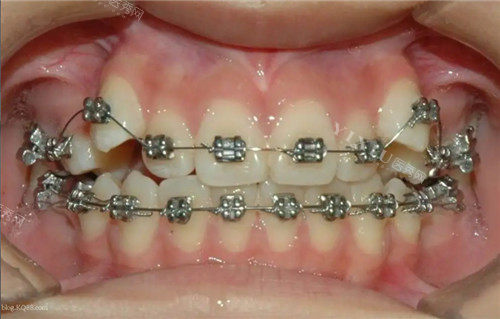

一、东营传统金属托槽矫正价格表:基础款性价比首要选择

传统金属托槽是矫正领域的经典选择,因结构简单、价格亲民,适合预算有限或牙齿问题不太复杂的人群。东营多家口腔机构 2025 年报价如下:

二、东营自锁托槽矫正价格表:舒适加速型选择

自锁托槽通过优化设计减少摩擦力,矫正周期更短、佩戴更舒适,适合对矫正时间有要求的人群。东营 2025 年主流报价: